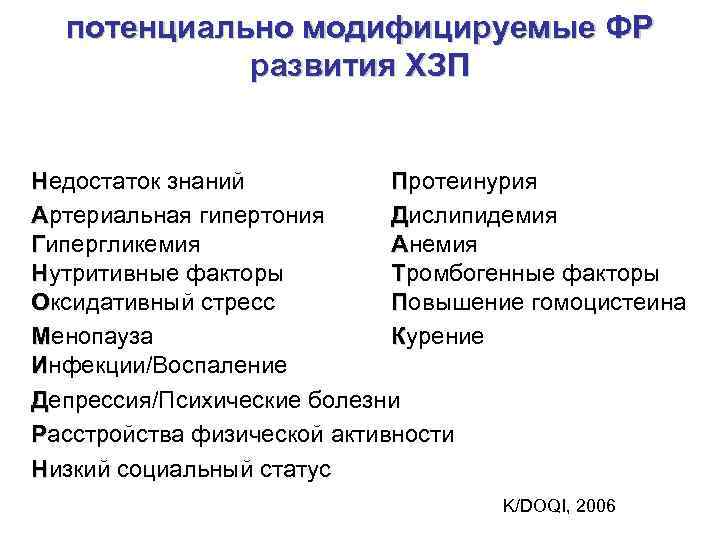

потенциально модифицируемые ФР развития ХЗП Недостаток знаний Протеинурия Артериальная гипертония Дислипидемия Гипергликемия Анемия Нутритивные факторы Тромбогенные факторы Оксидативный стресс Повышение гомоцистеина Менопауза Курение Инфекции/Воспаление Депрессия/Психические болезни Расстройства физической активности Низкий социальный статус K/DOQI, 2006

потенциально модифицируемые ФР развития ХЗП Недостаток знаний Протеинурия Артериальная гипертония Дислипидемия Гипергликемия Анемия Нутритивные факторы Тромбогенные факторы Оксидативный стресс Повышение гомоцистеина Менопауза Курение Инфекции/Воспаление Депрессия/Психические болезни Расстройства физической активности Низкий социальный статус K/DOQI, 2006